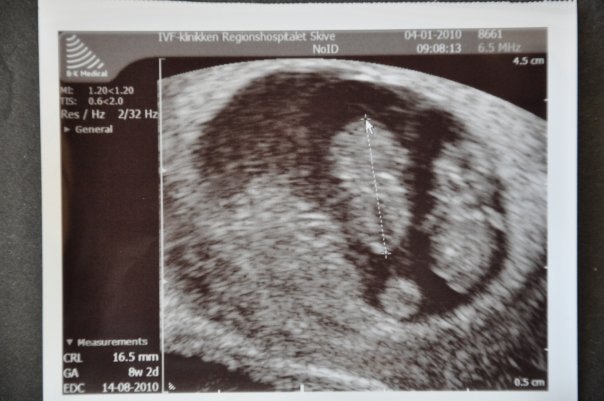

7+0 og man kan næsten ikke se den ene i sin sæk. Der var hjerteblink i begge. Lægen sagde, at han aldrig ville se efter hjerteblink før 7+0, da det bestemt ikke betød, at der ikke var liv, hvis man ikke kunne finde det.